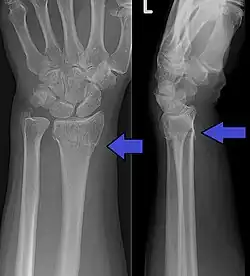

| An X-ray showing a Colles' fracture | |

Diagnosis can be made upon interpretation of anteroposterior and lateral views alone.[7]

The classic Colles fracture has the following characteristics:[8]

- Transverse fracture of the radius

- 2.5 cm (0.98 inches) proximal to the radio-carpal joint

- Dorsal displacement and dorsal angulation, together with radial tilt[9]

- Radial shortening

- Loss of ulnar inclination

- Radial angulation of the wrist

- Comminution at the fracture site

- Associated fracture of the ulnar styloid process in more than 60% of cases.